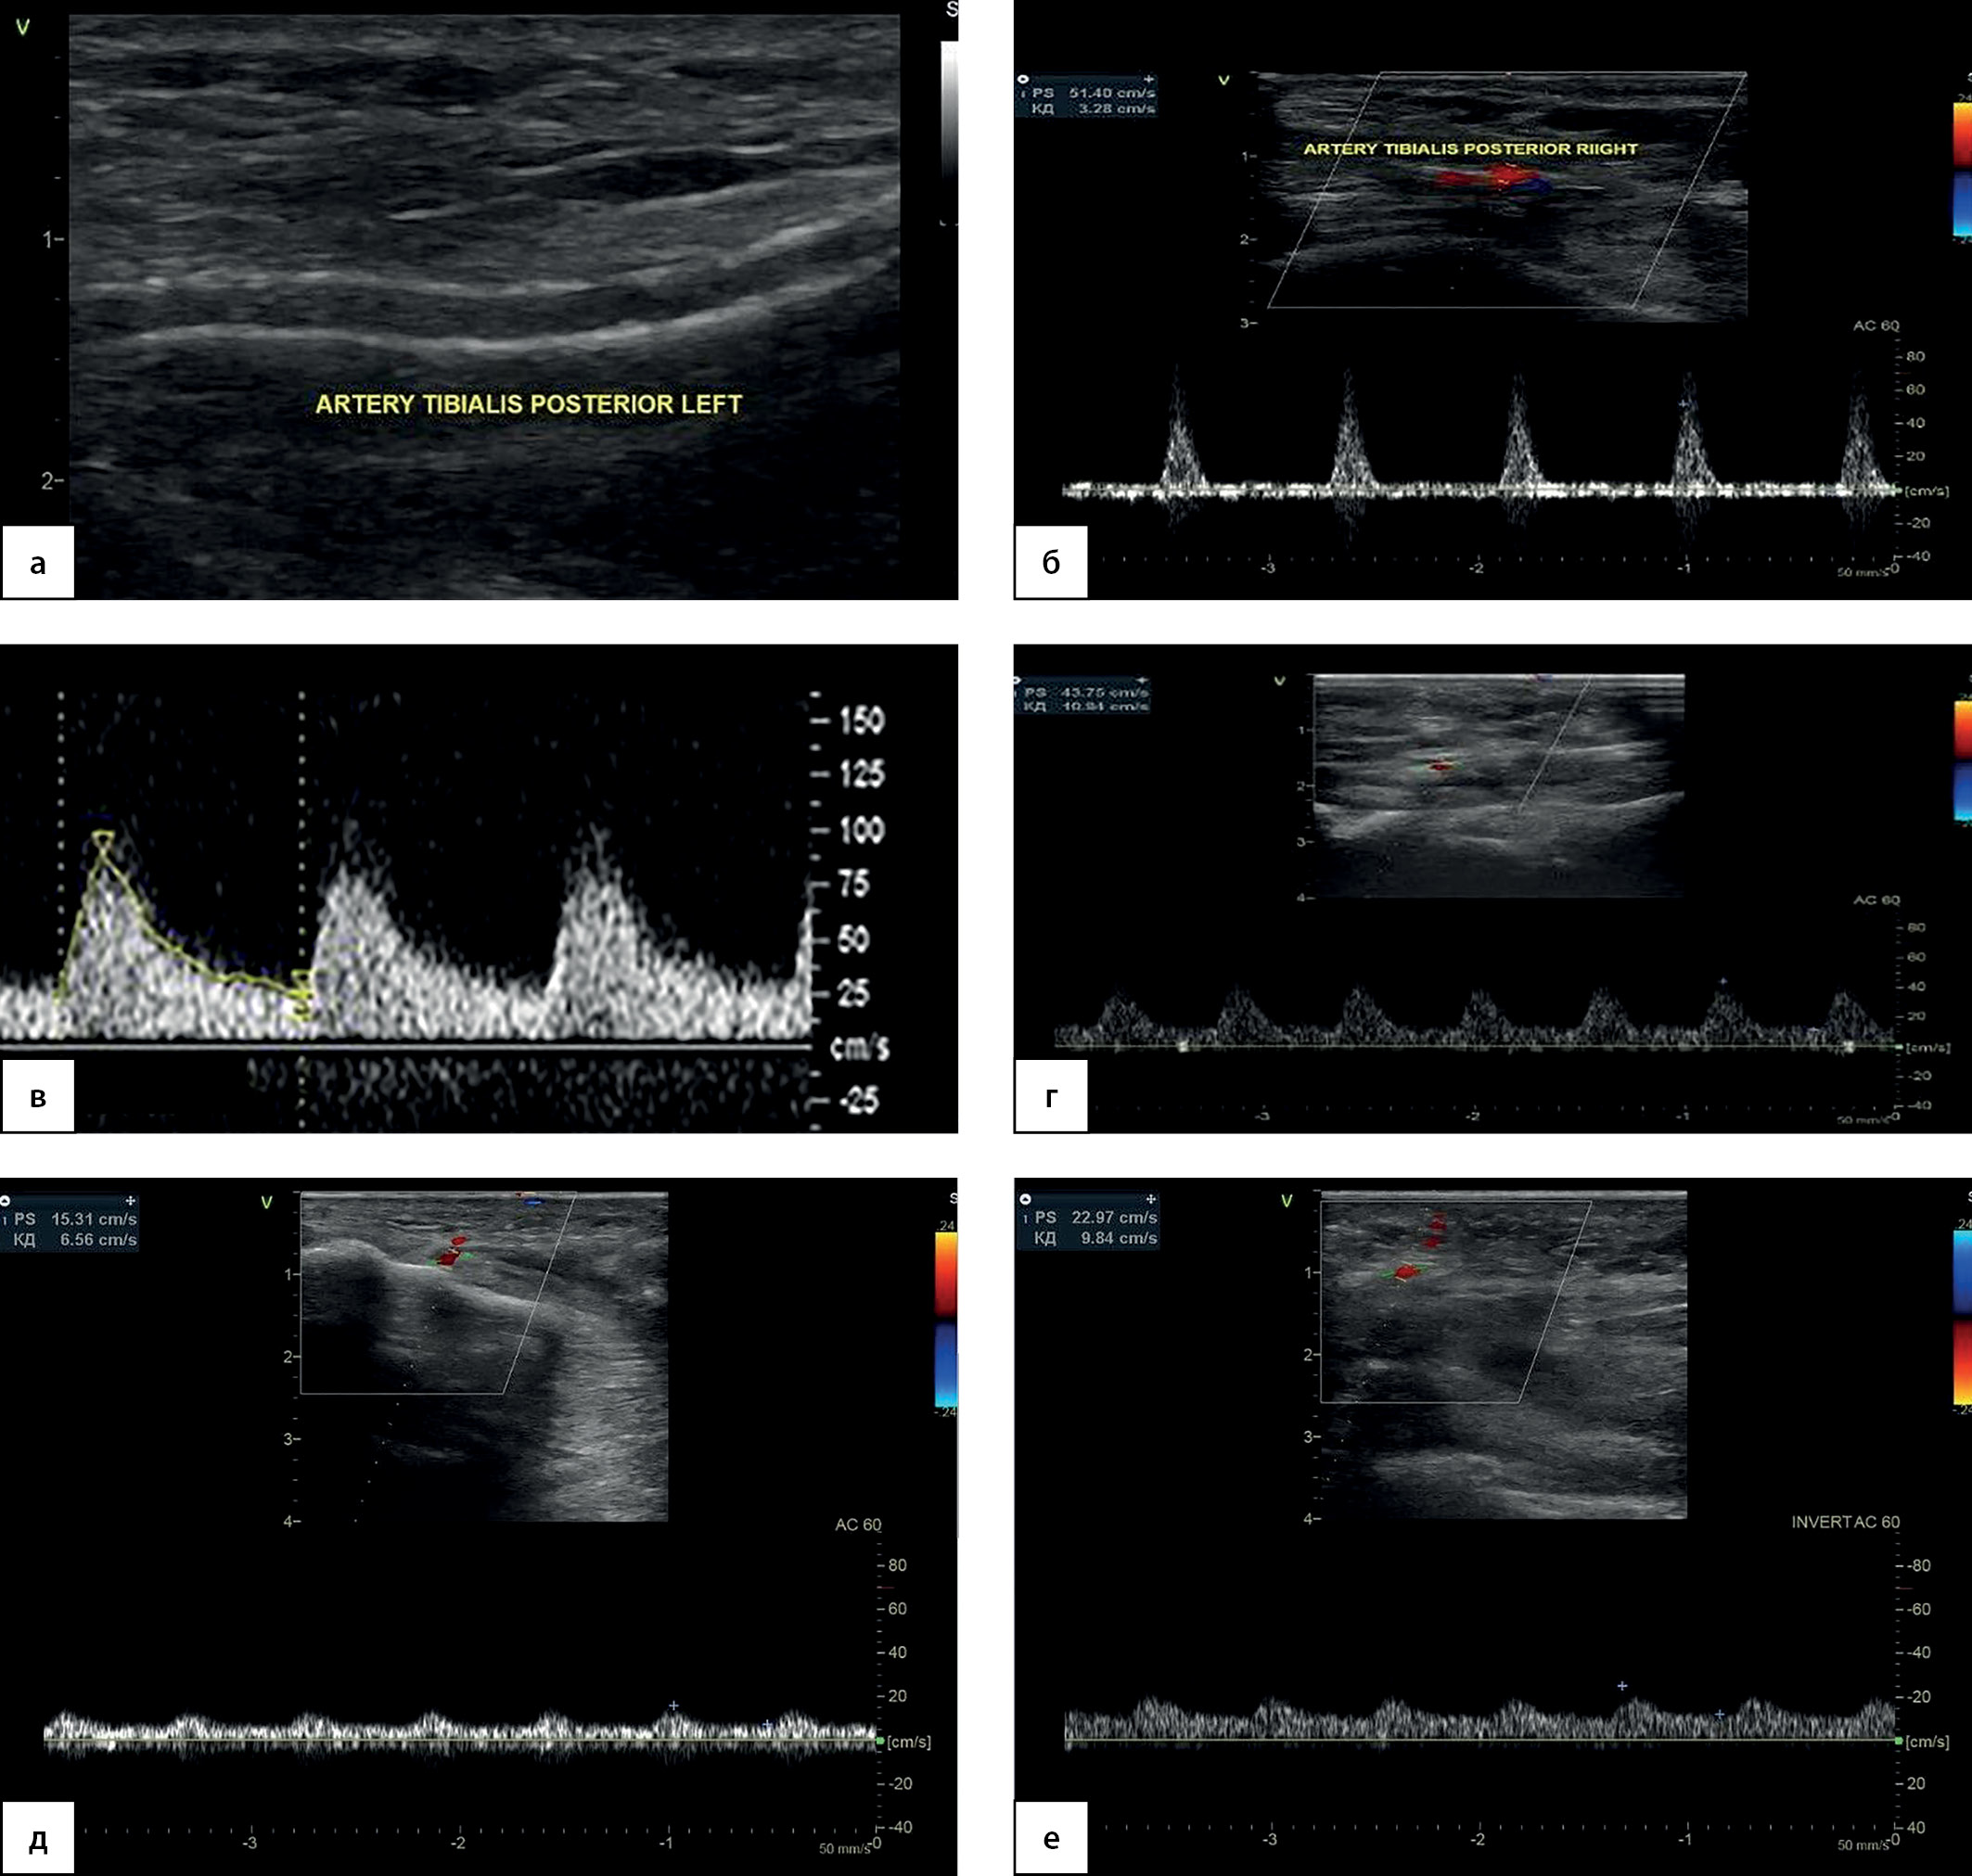

УЗДС артерий нижних конечностей

Заключение: атеросклероз магистральных артерий нижних конечностей. Эхографические признаки склероза Менкеберга (рис. 2а).

Справа: общая подвздошная и наружная подвздошная артерии (ОПА и НПА) — проходимы, стеноз 20–25% за счет мелких кальцинированных атеросклеротических бляшек (АСБ) по передней и задней стенкам. Общая бедренная артерия и глубокая артерия бедра (ОБА и ГАБ) — проходимы, перед бифуркацией ОБА и в устье ГАБ — циркулярная гиперэхогенная АСБ, стеноз 30%. Поверхностная бедренная артерия (ПБА) — в устье циркулярная гиперэхогенная АСБ, стеноз 20%, на протяжении по передней и задней стенкам диффузные АСБ, стеноз 30–40%. Стеноз подколенной артерии и тибиоперонеального ствола (ПкА и ТПС) до 30%. Задняя большеберцовая артерия и малоберцовая артерия (ЗББА и МБА) — визуализируется диффузное относительно равномерное повышение эхогенности сосудистой стенки в сочетании с утратой дифференцировки на слои. На всем протяжении — полисегментарное циркулярное обызвествление сосудистой стенки. По передней и задней стенкам лоцируются диффузные гиперэхогенные кальцинированные включения, мелкие кальцинированные АСБ, стенозы в верхней трети голени 50%, в средней и нижней трети голени — локальные стенозы до 80–90%. ЛСК по ЗББА 51 см/с в н/3 голени (рис. 2б). Передняя большеберцовая артерия (ПББА) — в устье и частично в верхней трети голени проходима, дистальнее ствол артерии не определяется (гипоплазия). Тыльная артерия стопы (ТАС) фрагментарно окклюзирована, кровоток коллатеральный, компенсированный, ЛСК — 88,6 см/с (рис. 2в). Латеральная подошвенная артерия (ЛПА) фрагментарно окклюзирована, кровоток коллатеральный, компенсированный, ЛСК — 43 см/с (рис. 2г). Кровоток по мелким артериям стоп: кровоток в 3-4-м межфаланговых промежутках (в области раны) по тыльным плюсневым (ТПА) и подошвенным плюсневым (ППА) артериям коллатеральный декомпенсированный, ЛСК — 21–22 и 14–15 см/с (рис. 2 д-е).

Рисунок 2. Ультразвуковое дуплексное сканирование

артерий нижних конечностей при поступлении.

а — выраженный кальциноз сосудистой стенки задней большеберцовой артерии правой нижней конечности. В-режим;

б — магистрально-измененный кровоток по задней большеберцовой артерии, линейная скорость кровотока — 51 см/с. Режим цветового допплеровского картирования, дополненный допплерографией;

в — коллатеральный компенсированный кровоток по тыльной артерии стопы, линейная скорость кровотока — 88,6 см/с. Режим допплерографии;

г — коллатеральный компенсированный кровоток по латеральной подошвенной артерии, линейная скорость кровотока — 43 см/с. Режим цветового допплеровского картирования, дополненный допплерографией;

д — коллатеральный декомпенсированный кровоток по тыльным плюсневым артериям в 4-м плюсневом промежутке, линейная скорость кровотока — 14–15 см/с. Режим цветового допплеровского картирования, дополненный допплерографией;

е — коллатеральный декомпенсированный кровоток по подошвенным плюсневым артериям в 4-м плюсневом промежутке, линейная скорость кровотока — 21–22 см/с. Режим цветового допплеровского картирования, дополненный допплерографией.

Таким образом, прицельное УЗДС в околораневой зоне позволило выявить значимое нарушение кровотока у нашего больного в зоне интереса. Полученные выводы необходимо подтвердить методами оценки перфузии мягких тканей стопы.

При контрольном УЗДС артерий 29.08.2022 г. отмечено восстановление кровотока по ЗББА, ЛПА, МБА и ТАС с остаточными стенозами по артериям голени до 50–60%. Регистрируется магистральный кровоток по ТАС, восстановление просвета и магистрально-измененного кровотока по ЛПА, а также по тыльным и подошвенным плюсневым артериям в 3–4 межфаланговых промежутках с оптимальной визуализацией их просвета (рис. 7).

Рисунок 7. Контрольное ультразвуковое дуплексное сканирование

артерий нижних конечностей.

а — Магистральный кровоток с низким периферическим сопротивлением по тыльной артерии стопы, прирост пиковой систолической скорости кровотока — с 56 до 89 см/с. Режим цветового допплеровского картирования, дополненный допплерографией.

б — Латеральная подошвенная артерия, равномерное окрашивание просвета. Режим энергетического допплеровского картирования, дополненный допплерографией.

в — Магистральный кровоток по латеральной подошвенной артерии, пиковая систолическая скорость кровотока — 40 см/с. Режим энергетического допплеровского картирования, дополненный допплерографией.

г — Магистрально-измененный кровоток по тыльной плюсневой артерии в 4-м плюсневом промежутке, прирост пиковой систолической скорости кровотока — с 15 до 66 см/с. Режим цветового допплеровского картирования, дополненный допплерографией.

д — Подошвенная плюсневая артерия в 4-м плюсневом промежутке после реваскуляризации. Режим цветового допплеровского картирования.